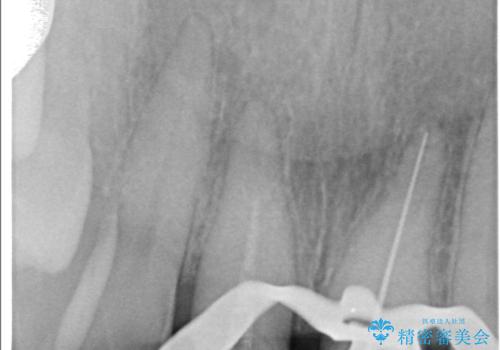

- 気を失って転倒し、前歯をぶつけたことをきっかけに「かかりつけ医で抜歯と診断された」との主訴で来院された患者様です。

レントゲン撮影や顕微鏡下での精査、メチレンブルーによる染色検査を行った結果、破折線は認められず、保存可能と判断しました。

精密根管治療を行い、その後オールセラミッククラウンで審美的に修復しています。あわせてホワイトニングとエアフローによるクリーニングも行い、自然で美しい仕上がりとなりました。